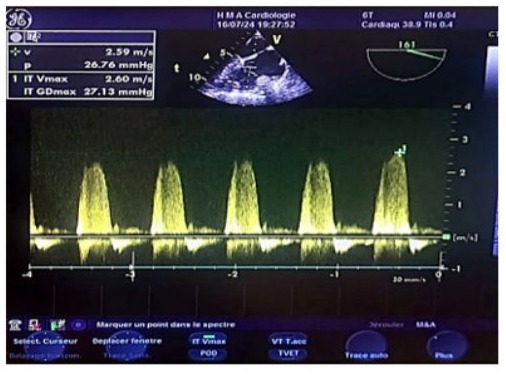

Figure 18: Continuous wave Doppler transesophageal echocardiography (TOE) image of the vena contracta in tricuspid regurgitation (reflux within the tricuspid annulus), showing a normal systolic pulmonary artery pressure estimated at 38 mmHg, with a maximum tricuspid regurgitation velocity of 2.60 m/s. The estimated pulmonary artery diastolic pressure (POD) is 10-15 mmHg, and the tricuspid gradient is 27 mmHg.